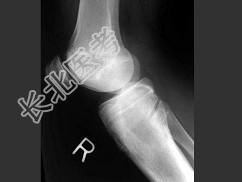

- 单项选择题女,13岁, 右膝部痛,结合图像, 最可能的诊断是 ( )

A、胫骨近端动脉瘤样骨囊肿

B、胫骨近端成软骨细胞瘤

C、胫骨近端骨巨细胞瘤

D、胫骨近端内生软骨瘤

E、以上都不是